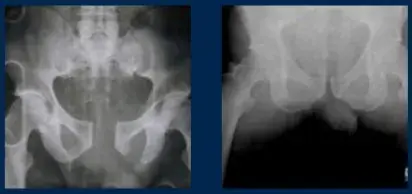

- Efectiva: La TPOD ha sido probada para conseguir la fijación definitiva en la reducción de la diástasis del pubis

Radiografías antes y después de usar T-Pod®